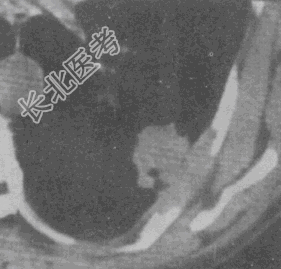

- 单项选择题女,65岁, 胸透发现左肺病灶,CT检查如图, 最可能的CT诊断为

A、慢性炎症

B、淋巴瘤

C、炎性假瘤

D、中心型肺癌

E、周围型肺癌